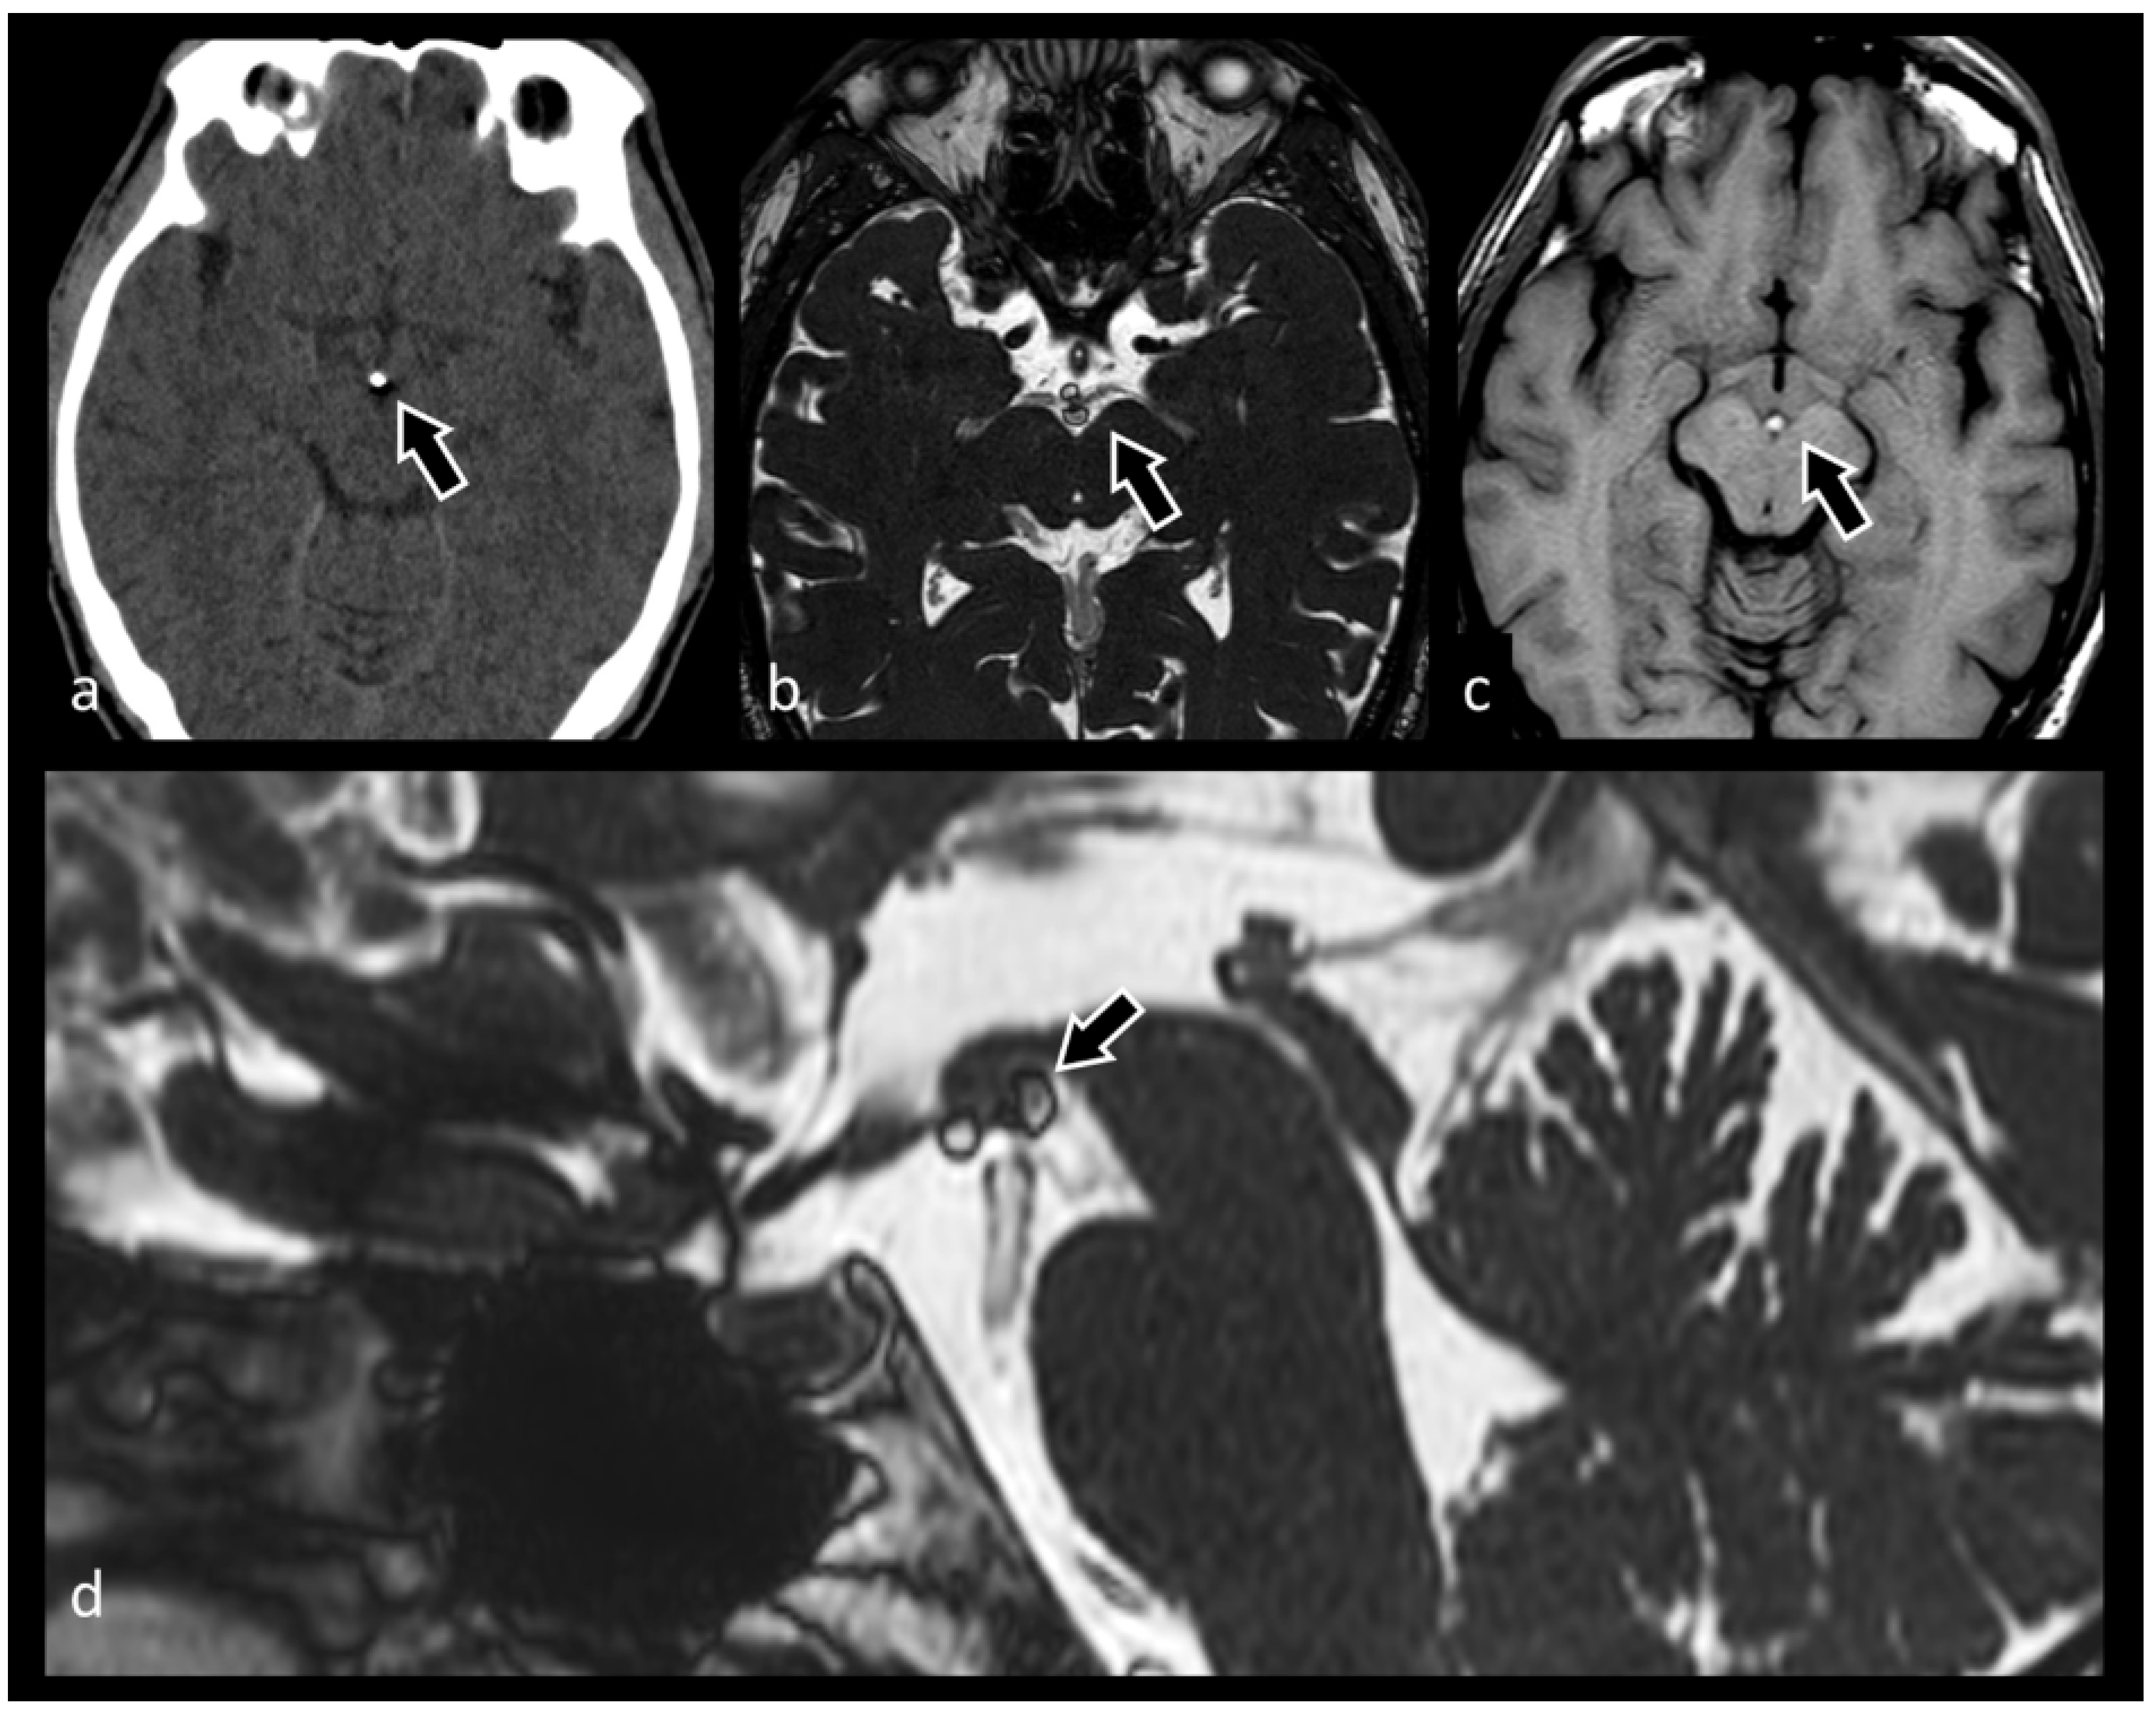

3.6. Neurocysticercosis

- Carrillo Mezo, R.; Lara García, J.; Arroyo, M.; Fleury, A. Relevance of 3D magnetic resonance imaging sequences in diagnosing basal subarachnoid neurocysticercosis. Acta Trop. 2015, 152, 60–65. [Google Scholar] [CrossRef] [PubMed]

- Govindappa, S.S.; Narayanan, J.P.; Krishnamoorthy, V.M.; Shastry, C.H.; Balasubramaniam, A.; Krishna, S.S. Improved detection of intraventricular cysticercal cysts with the use of three-dimensional constructive interference in steady state MR sequences. AJNR. Am. J. Neuroradiol. 2000, 21, 679–684. [Google Scholar] [PubMed]